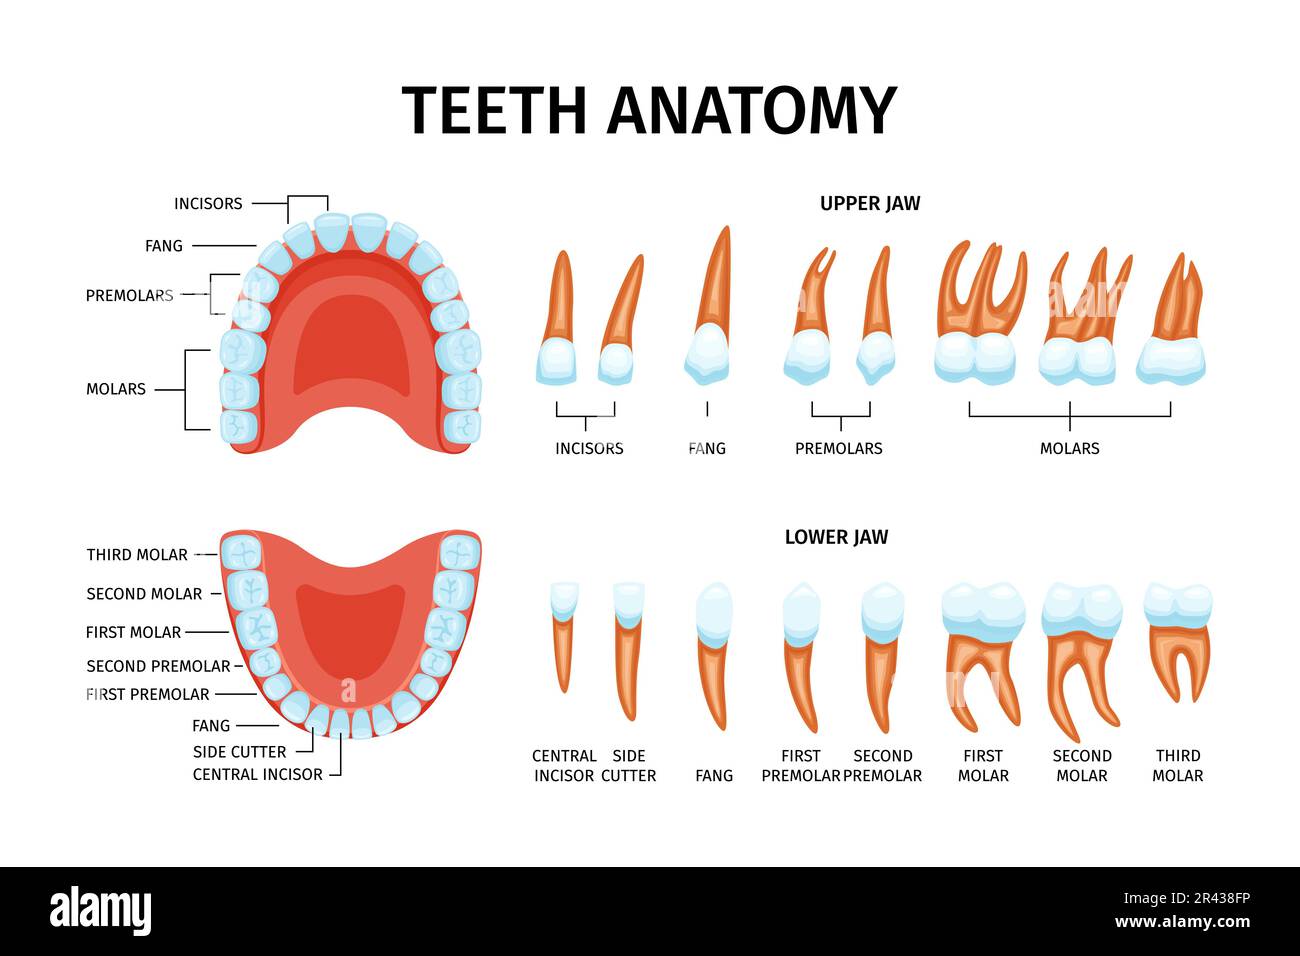

Discover the sophistication of annotated illustration of the jaw's anatomy | stable diffusion online with our curated gallery of numerous images. featuring elegant examples of photography, images, and pictures. ideal for luxury lifestyle publications. Browse our premium annotated illustration of the jaw's anatomy | stable diffusion online gallery featuring professionally curated photographs. Suitable for various applications including web design, social media, personal projects, and digital content creation All annotated illustration of the jaw's anatomy | stable diffusion online images are available in high resolution with professional-grade quality, optimized for both digital and print applications, and include comprehensive metadata for easy organization and usage. Our annotated illustration of the jaw's anatomy | stable diffusion online gallery offers diverse visual resources to bring your ideas to life. Professional licensing options accommodate both commercial and educational usage requirements. Cost-effective licensing makes professional annotated illustration of the jaw's anatomy | stable diffusion online photography accessible to all budgets. Regular updates keep the annotated illustration of the jaw's anatomy | stable diffusion online collection current with contemporary trends and styles. Multiple resolution options ensure optimal performance across different platforms and applications. Time-saving browsing features help users locate ideal annotated illustration of the jaw's anatomy | stable diffusion online images quickly. Whether for commercial projects or personal use, our annotated illustration of the jaw's anatomy | stable diffusion online collection delivers consistent excellence.